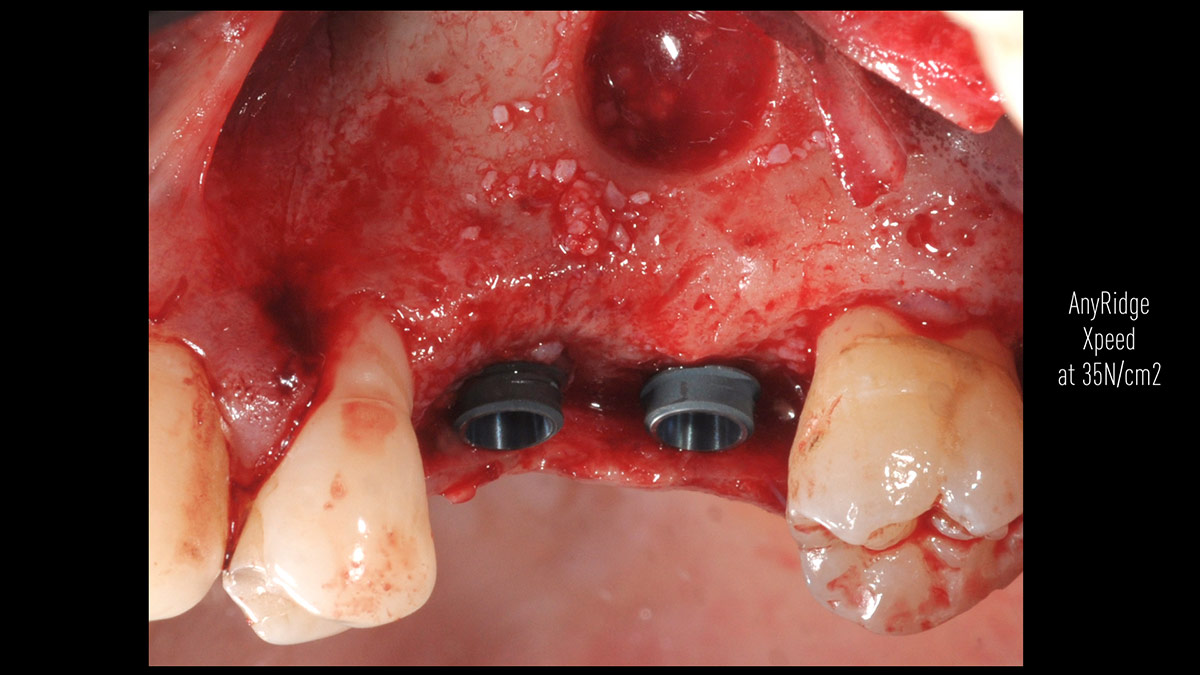

Delayed implant placement; sinus floor elevation by means of lateral approach and implant placement with GBR. Case report by Irfan Abas, M.Sc.